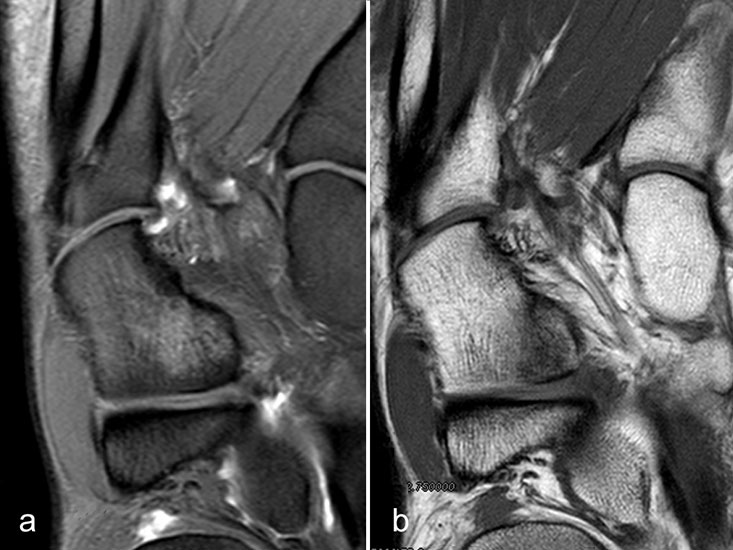

Gicht

Typische Gichtmanifestation an der Großzehe mit Tophusstachel (Pfeil) und großem Tophus, in welchem Uratablagerungen identifiziert werden können (Pfeilspitze). T1-gewichtete Sequenz vor (a) und nach (b) Kontrastmittelgabe, letztere mit Fettsuppression.

Abbildung 15

Dies erst recht, wenn diese Arthritis am Großzehen­grundgelenk auftritt (Abb. 15). In diesen Fällen sollte man den Verdacht auch dann aufrechterhalten, wenn die MRT nur eine unspezifische Entzündung zeigt und die Harnsäurewerte, die starken Schwankungen unterliegen können, nicht erhöht sind.

Spezifische MR Befunde finden sich erst bei der chronischen Gicht, wenn sich in T2 sehr signalarme Kristallablagerungen und Gicht-Tophi bilden. Letztere führen dann häufig zu den aus der Röntgendiagnostik bekannten gelenkfernen Erosionen.

Abbildung 15: Typische Gichtmanifestation an der Großzehe mit Tophusstachel (Pfeil) und großem Tophus, in welchem Uratablagerungen identifiziert werden können (Pfeilspitze). T1-gewichtete Sequenz vor (a) und nach (b) Kontrastmittelgabe, letztere mit Fettsuppression.